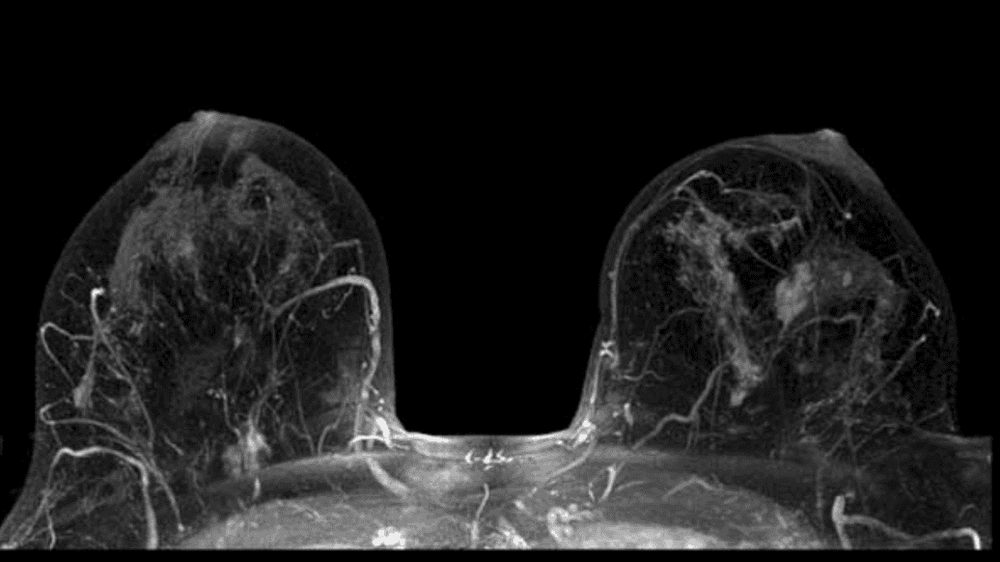

3.5 MRI của vú

MRI có thể được sử dụng với chụp nhũ ảnh để phát hiện ung thư vú, đặc biệt ở những phụ nữ có mô vú dày đặc hoặc những người có nguy cơ mắc bệnh cao.